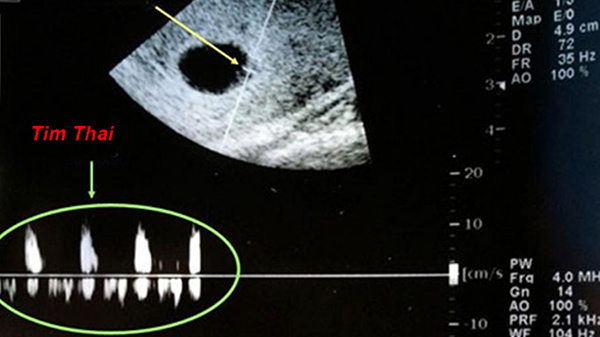

Thời kì mang thai của mẹ sẽ kéo dài 9 tháng 10 ngày, tức là vào khoảng 40 tuần. Theo ý kiến của các bác sĩ chuyên khoa thì vào tuần thứ 6 đến thứ 7 của thai kì thì mẹ có thể nghe thấy tim thai qua dụng cụ chuyên dụng của bệnh viện.

Tim thai được đánh giá là bộ phận được hình thành sớm nhất, chỉ trong vòng tuần các cấu trúc như ống tim, vách ngăn đã dần xuất hiện. Để phát hiện các mạch lớn và dòng máu chuyển động theo nhịp đập của tim thai bác sĩ sẽ tiến hành siêu âm Doppler.

Đôi khi nguyên nhân không nghe thấy tim thai không xuất phát từ bản thân người mẹ mà là do thiết bị độ nhạy kém, ống nghe không chuẩn, lựa chọn phương pháp siêu âm không phù hợp. Ví dụ như nếu bác sĩ sử dụng phương pháp siêu âm ổ bụng thì sẽ rất khó phát hiện ra tim thai, phương pháp phù hợp nhất trong tình huống này chính là siêu âm đầu dò.